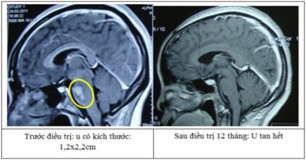

Tính đến nay có gần 4000 u não và bệnh lý sọ não được điều trị thành công bằng kỹ thuật sử dụng dao gamma quay và nhiều bệnh nhân không phải ra nước ngoài điều trị.

![]() |

| Kỹ thuật sử dụng dao gamma quay là kỹ thuật xạ phẫu tiên tiến trên thế giới, đưa Việt Nam trở thành một trong những nước đầu tiên trong trị u não |